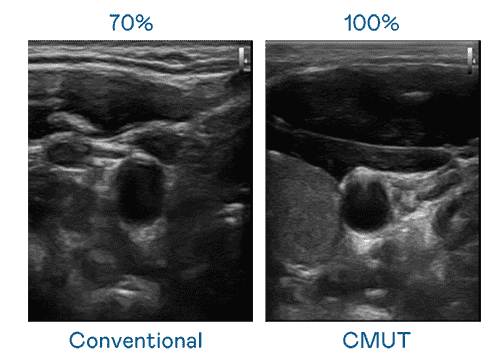

CMUT 技术是一种用电容式微机电元件来产生超音波讯号的技术。。与传统 PZT 压电式技术相比,,CMUT 频宽增加 30%,,,,更宽频的超音波讯号让影像解析度大幅提升,,,是实现高影像品质医疗超音波扫描、、、促进精准医疗发展的关键技术。。

大频宽带来超清晰影像

超音波影像的解析度高低,,首先取决于探头能发出的讯号频宽。。www.z6.com CMUT 可提供高清晰的超音波讯号,,,提供高频宽、、、高灵敏度、、影像纹理细节更高的超音波影像,,,,协助医护人员缩短影像判读时间及利用精准的医疗影像进行诊断。。。。